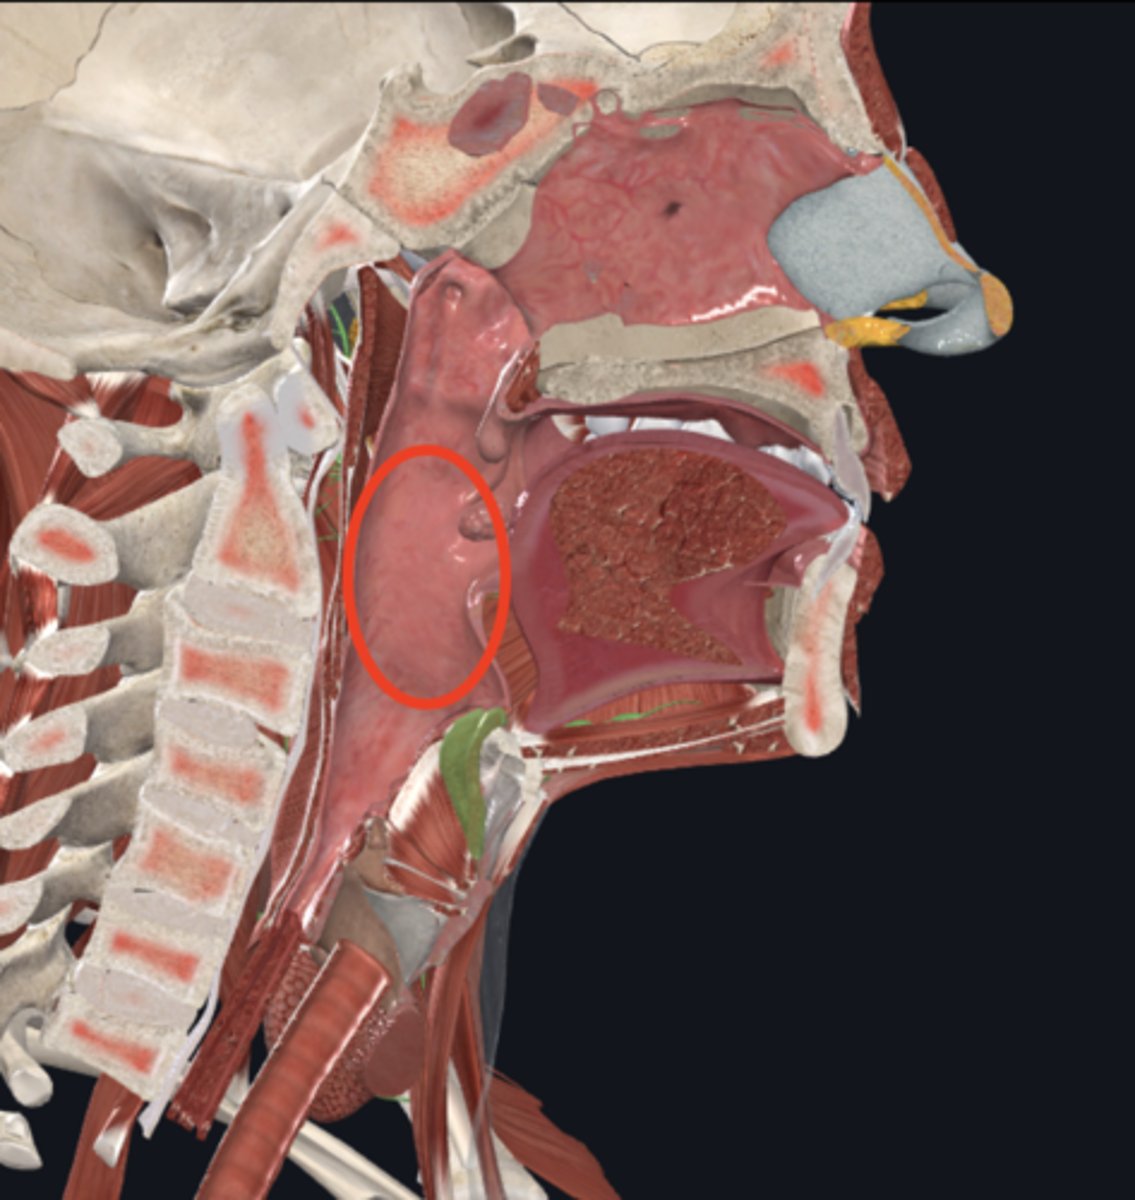

name the circled region

oropharynx

name the circled region